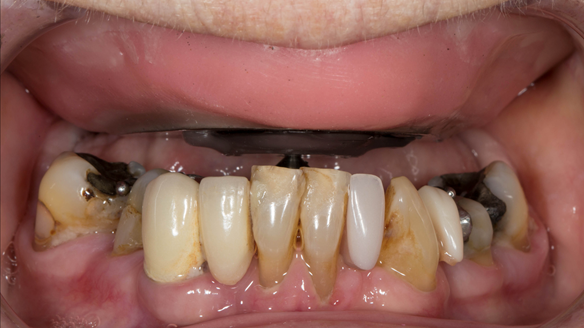

- The remaining natural upper natural teeth and lower back molars were heavily restored having generalised periodontitis stage 4 Grade C. Some of the teeth exhibited caries. The prognosis for these teeth ranged from dubious to hopeless.

- The upper and lower acrylic based partial dentures exhibited suboptimal extension of the flanges and saddles. They had poor retention, support, stability and tissue fit.

The clinical situation and treatment process is shown in detail below with photographs. In addition, threre is a link to the a 45 minute webinar I gave explaing this case. I provided the clinical work and Rowan Garstang provided the technical work.